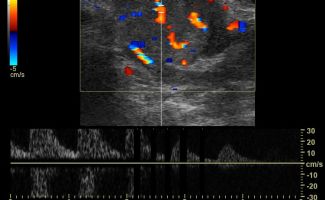

Πολλές αλλοιώσεις και παθήσεις μπορούν να απεικονιστούν υπερηχογραφικά και να μελετηθούν αξιόπιστα με τη βοήθεια του Έγχρωμου Doppler και της Ελαστογραφίας .

- Αιμαγγειώματα, αγγειοδυσπλασίες (αγγειακού τύπου βλάβες)